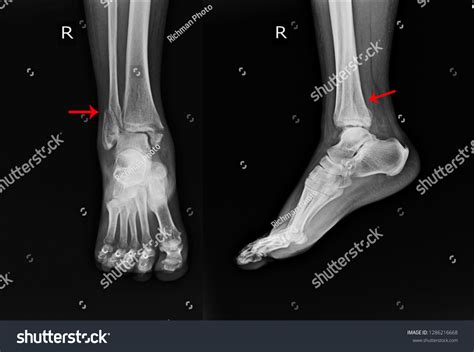

A doctor will typically start by physically examining the foot and ordering imaging tests. An X-ray is the standard tool to confirm a top broken foot, though in some instances of stress fractures, an MRI or CT scan may be necessary to see the damage more clearly.

• top of foot broken pictures